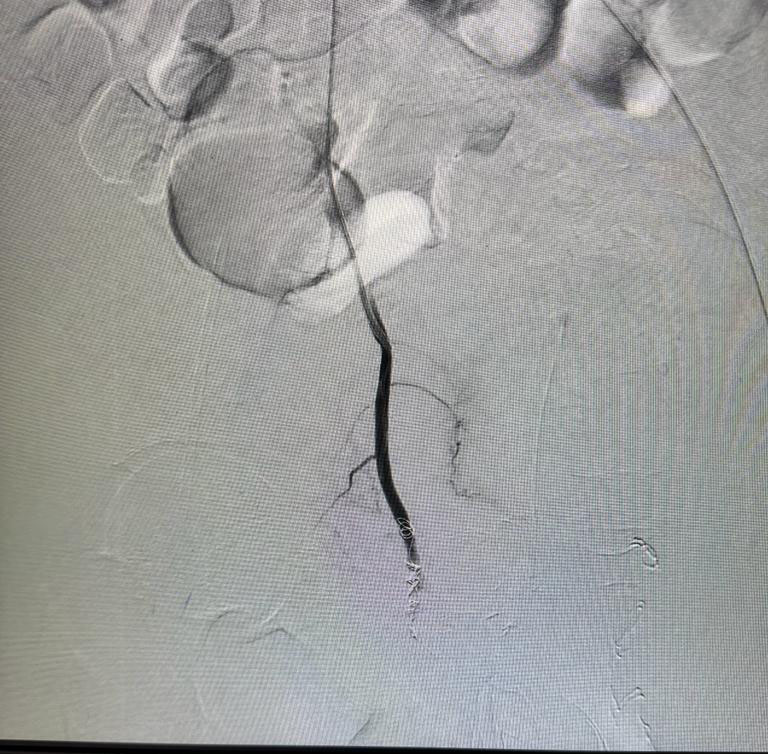

Vascular embolization of arteriovenous malformation